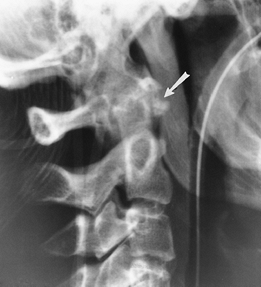

FIGURE 3-10

Hyperextension injury C1. Lateral radiograph of the upper cervical spine demonstrates an avulsion fracture of the anterior arch of C1 (arrow). |